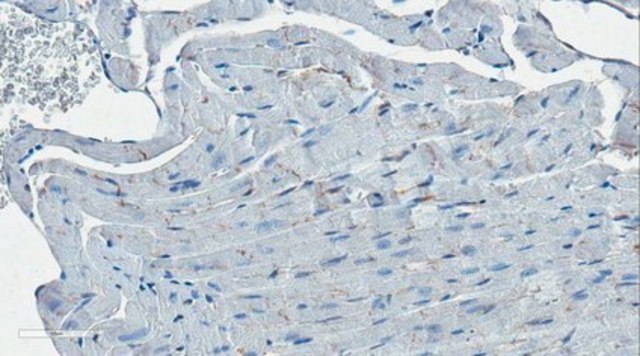

Immunohistochemistry Analysis: A representative lot immunostained intercalated discs in myocardial sections from adult wild-type, but not iASPP-deficient (iASPPΔ8/Δ8) mice (Notari, M., et al. (2015). Proc. Natl. Acad. Sci. U. S. A. 112(9):E973-E981).

Note: iASPP is expressed at intercalated discs. To prepare heart tissue sections for iASPP staining, it is important to cut the tissues at an angle parallel to the plane of the intercalated discs.

Clone LX128.5 immunostained intercalated discs in myocardial sections from wild-type, but not iASPP-deficient (iASPPΔ8/Δ8) adult mice (Notari, M., et al. (2015). Proc. Natl. Acad. Sci. U. S. A. 112(9):E973-E981).

Evaluated by Immunohistochemistry in mouse heart tissue.

Immunohistochemistry Analysis: A 1:50 dilution of this antibody detected iASPP in mouse heart tissue.